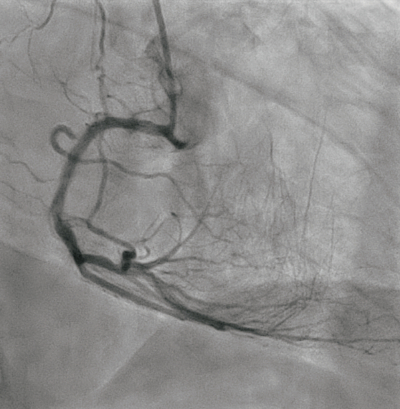

冠動脈造影像 を別に示す。血圧が低下したため、補助循環装置を挿入した。このときの胸部透視時の写真を別に示す。

a. 冠動脈造影では冠動脈の中隔枝を介した側副血行が認められる。

b. 冠動脈造影では右冠動脈の近位部に高度狭窄を認める。